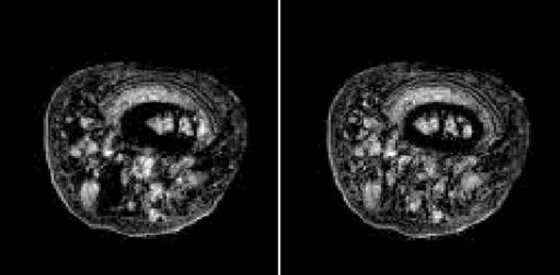

Bei allen Schritten einer NMR-Bildgebungssequenz können Bildartefakte entstehen. Die wichtigsten sind Partialvolumen-Effekte (›Verschmieren‹ des Bildes bzw. Überlagerung verschiedener Strukturen bei Variationen der Probenstruktur innerhalb der angeregten Schicht), chemische Verschiebungsartefakte (vor allem beim Lesegradienten, siehe Abb. 4) und Flußartefakte (beim Phasengradienten). Kompliziertere Artefakte können durch das Zusammenspiel von Diffusion und lokalen Suszeptibilitätsunterschieden in der Probe entstehen (NMR-Diffusions- und Bewegungseffekte).Anwendungsgebiete: Die bekannteste Anwendung der NMR-Bildgebung liegt in der medizinischen Diagnostik (siehe Abb. 5 und Abb. 6, Kernspintomograph). Daneben wird sie jedoch auch zunehmend in der biologischen Grundlagenforschung sowie für die Untersuchung von Proben aus den Materialwissenschaften, der chemischen Prozeßtechnik und der Lebensmitteltechnologie angewandt. Die speziellen Vorteile der Kernspintomographie für alle diese Bereiche sind vor allem die Zerstörungsfreiheit sowie die Vielfalt an möglichen Kontrastparametern, die mit ein und derselben Methode untersucht werden können.

Kernspintomographie 4: Verschiebungsartefakte des Fettsignals aus dem Knochenmark in einem menschlichen Finger; rechtes Bild: Verschiebungsarktefakt korrigiert.